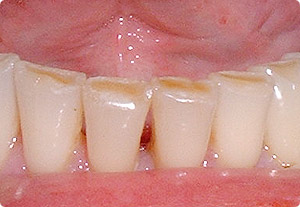

Grund: Harte Zahnbürsten

-- Zahnfleischrückgang kommt aber auch von zu harten

Zahnbürsten, wenn zu viel gebürstet wird [1]

Zahnbürsten dürfen nicht zu harte

Borsten haben. Eigentlich sollte die

Produktion harter Zahnbürsten verboten sein. |